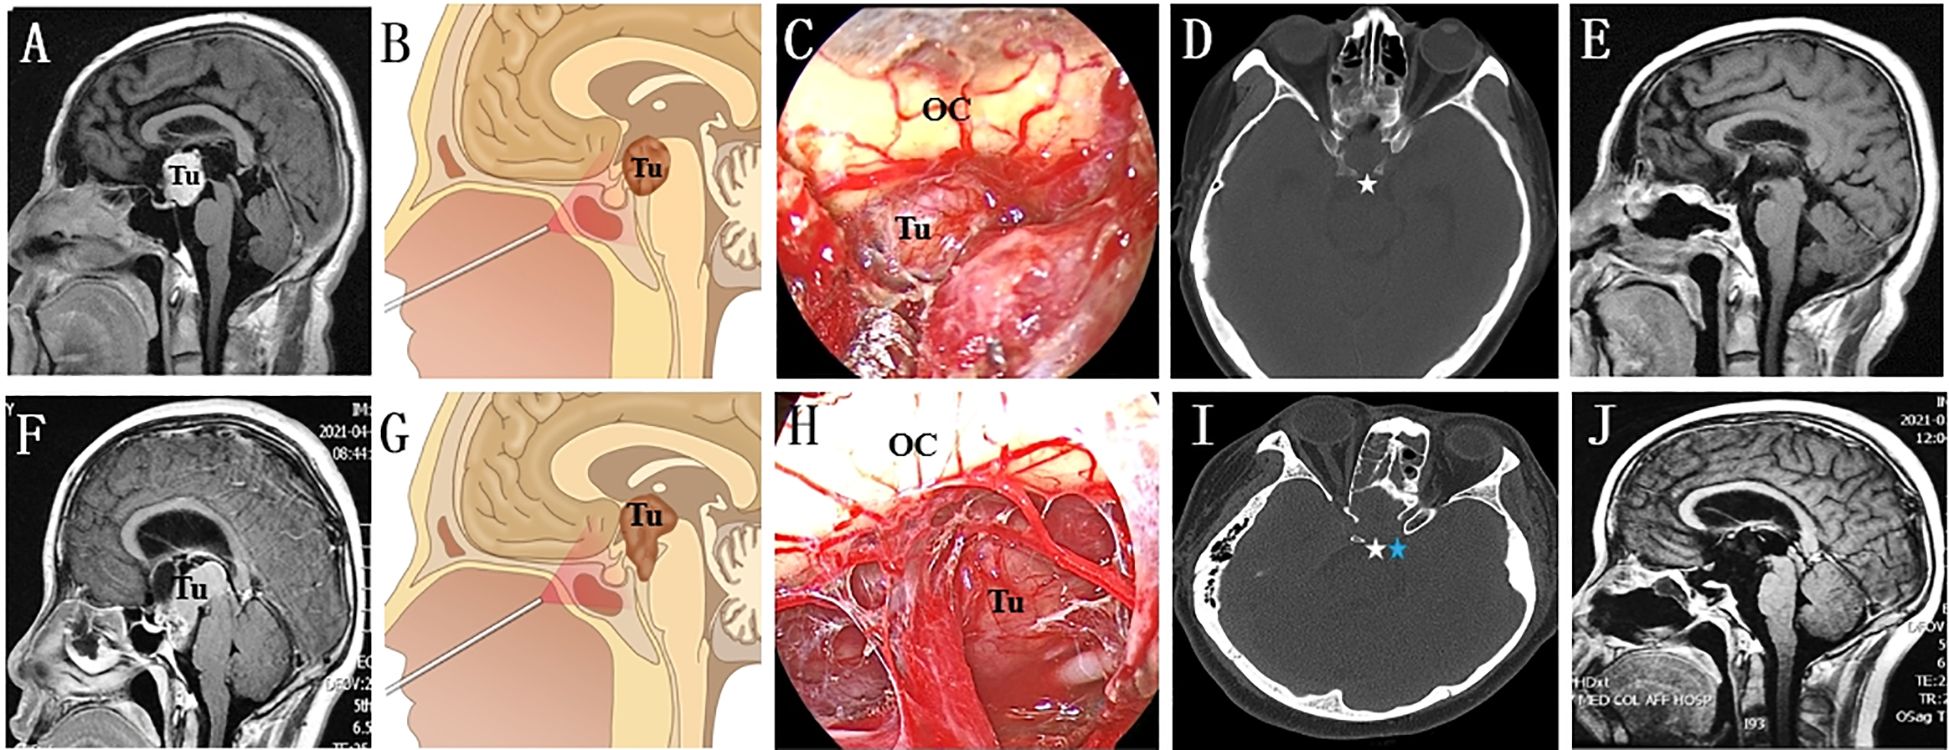

The decision to perform dorsectomy and/or posterior clinoidectomy is contingent on the involvement of the tumour. If the tumour (Figure 3) extends downwards and occupies the prepontine areas, a second sellar floor dura incision, unilateral dorsectomy and posterior fossa dura incision are needed following PGT. For lesions with lateral extension or involving the interpeduncular cistern, the ipsilateral side of the PCP, which is detached from the upper clivus when the dorsum sellae is drilled out, must be carefully removed to create additional working space in the interpeduncular cistern.

Figure 3. Endoscopic endonasal intradural pituitary transposition for resecting retroinfundibular lesions. (A, B) The tumour is located retroinfundibularly and extends inferiorly into the prepontine areas. (C) The infrachiasmatic space was narrow, and the tumour was blocked by the PG and DS. (D) The DS was individually drilled out (white arrow) and confirmed by a postoperative thin-layer CT scan. (E) Follow-up MR image showing that the tumour was radically resected. (F, G) This retroinfundibular tumour was very large and occupied both the prepontine and interpeduncular cisterns. (H) Except for the DS, the surgical corridor was effectively enlarged by removing the left PCP. (I) The left DS (white arrow) and PCP (blue arrow) disappeared on the postoperative thin-layer CT scan. (J) Follow-up MR image showing no residual tumour or occurrence. Tu, tumour; OC, optic chiasma.